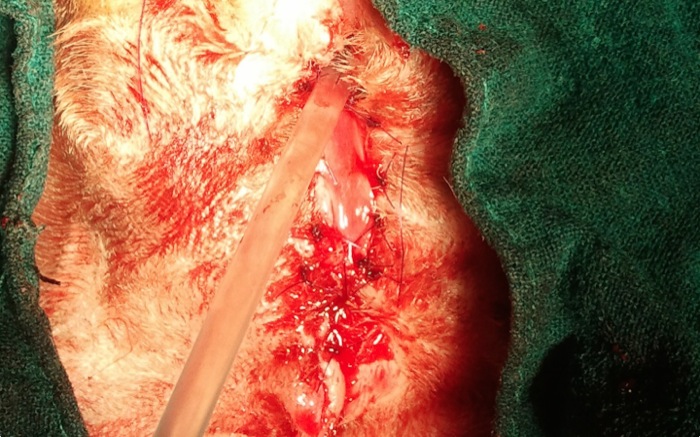

La necrosis observada incluye escroto, prepucio y área colindante.

Tras retirar el escroto y prepucio necrótico se comprueba que también el pene lo está. Se castra de un testículo inguinal y del otro que se había retraído hacia el interior ante la necrosis del escroto. Una vez limpio de tejido muerto y castrado podemos empezar con la uretrostomía.

Ante posibles infecciones ascendentes y dado que no es un caso de obstrucción se ve contraproducente realizar la disección hasta las glándula bulbouretrales como habitualmente se hace. Además al no profundizar tanto en el canal pélvico preservamos mas la función nerviosa dado que aún no se ha generado incontinencia fecal o urinaria.